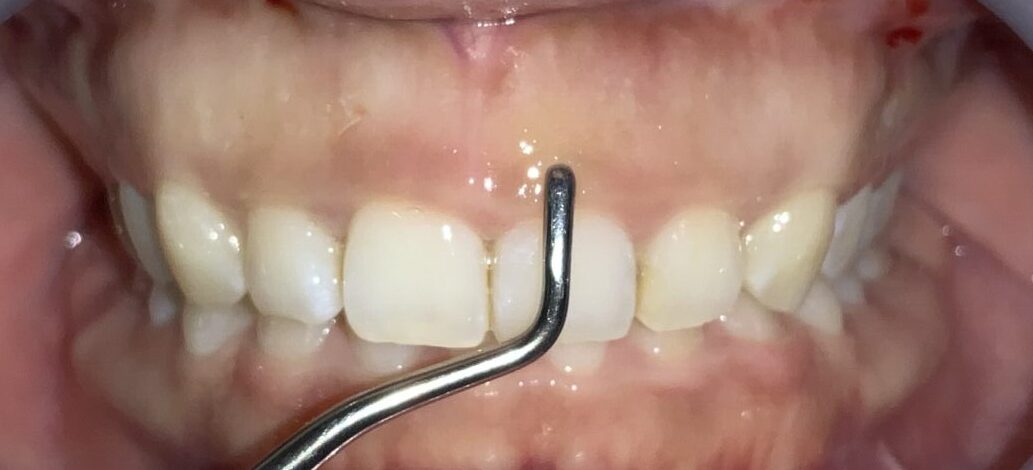

今回の患者様の治療前の状態です。

歯ぐきの長さに比較して、歯が少し小さいですね。歯ぐき自体は健康で綺麗なピンク色をしています。

一番気になる、前歯の歯と歯ぐきの位置状態の検査します。

こんなに歯ぐきがかぶさっています。